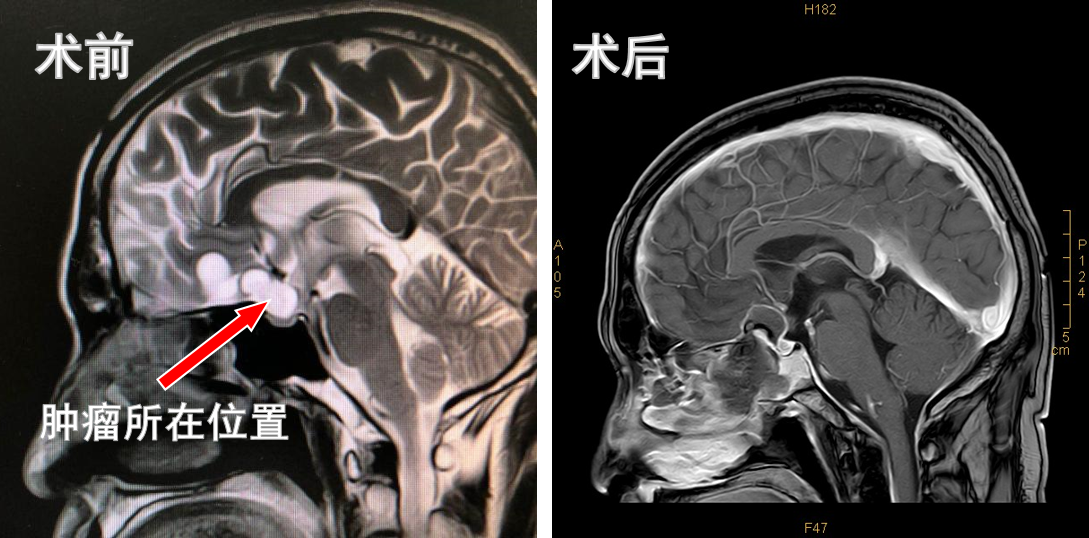

神经外科以颅咽管瘤术后复发将乔某收入院。由于患者有开颅手术史,复发肿瘤大小约38.6*18.0*24.3mm,较上次大且压迫视交叉神经,出现视力下降,再次手术的风险及并发症较第一次手术来说更高。科主任吴震高度重视,带领医护人员多次开展病例讨论,并与眼科、神经内科、麻醉科、内分泌科等进行多学科联合会诊后,制订详细的手术方案及围手术期注意事项。

7月21日,神经外科手术团队为患者实施了神经内镜下经鼻蝶窦复发颅咽管瘤切除术,术中发现瘤体比预想的还大,血运丰富且与周围组织黏连紧密,这对手术操作的精细程度提出更高要求。经过认真辨别,仔细分离,逐步将肿瘤全部切除,成功保护了视神经、颈内动脉等重要结构。为防止脑脊液瘘形成,术后第二日为患者行腰椎置管术引流脑脊液,同时采取了调节激素用量、准确记录出入量、监测电解质变化等治疗措施。经过神经外科团队缜密的术前准备,细致的术中操作,周密的术后管理及相关科室的大力配合,患者病情逐渐稳定,并发症得到有效控制,左眼视力已有光感,右眼视力良好,无脑脊液鼻漏形成,复查头颅核磁显示肿瘤完全切除,视交叉受压缓解,相关激素等化验指标未见明显异常,患者对治疗效果满意,已于近日顺利出院。